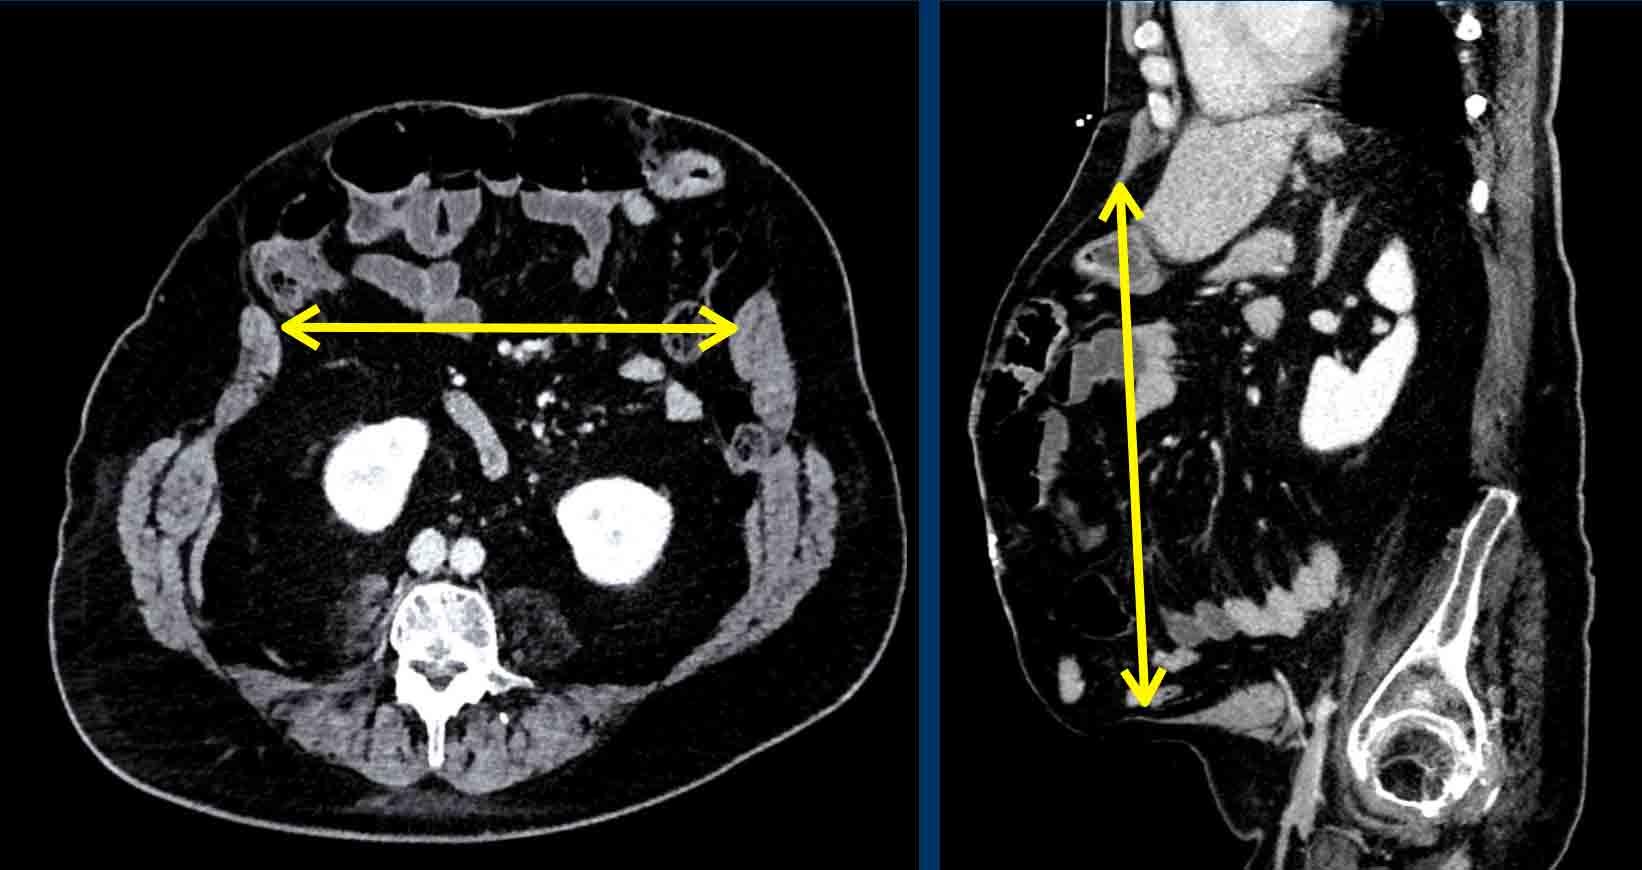

Vị trí và kích thước của khiếm khuyết

Mô tả kích thước khiếm khuyết thành bụng là cần thiết cho việc lập kế hoạch phẫu thuật trước mổ.

Kích thước bao gồm chiều rộng và chiều cao.

Hình minh họa sơ đồ đo khiếm khuyết theo hai trục: trục dọc và trục ngang (xem Hình).

Đây là ví dụ về cách đo kích thước khiếm khuyết.

Chiều rộng thoát vị là khoảng cách tối đa giữa hai cơ thẳng bụng, được đo trên mặt cắt ngang tại vị trí có khoảng cách lớn nhất.

Chiều cao khiếm khuyết là khoảng cách tối đa theo chiều đầu-đuôi, được đo trên mặt cắt đứng dọc.